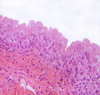

Pseudostratified Columnar

11